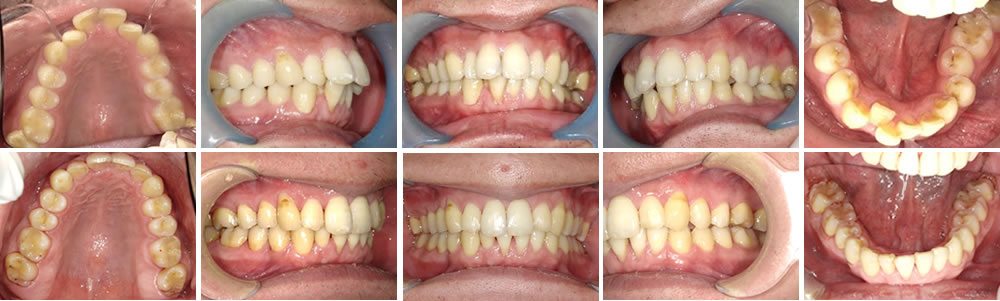

マウスピース矯正(インビザライン)で反対咬合・ガタツキを改善した症例

年齢

50代

性別

女性

症例を見る

マウスピース矯正(インビザライン)で過蓋咬合・前歯の叢生を改善した症例

30代

男性

マウスピース矯正(インビザライン)で叢生を改善した症例